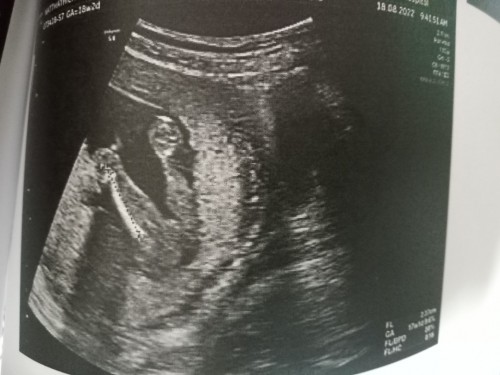

หน้าจะ ญ .ของเค้า ญ 34สัปดา